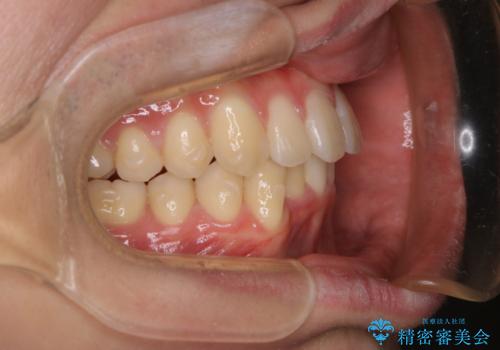

- 口元の突出感は気にならないが、上の前歯の角度と、下の前歯のがたつきが気になるとご相談にいらした方です。なるべく費用や治療期間を抑えて治療したいとのご希望に合わせて治療を計画しました。

この患者様への治療方針として、奥歯から少しずつ歯を移動させる方法と、歯をわずかに削って並べる方法とをご提案しました。短期間での治療を望まれたため、歯をサイズダウンさせて歯を並べました。わずかではあるものの、削った歯は元には戻せないことを十分ご説明し、ご理解ご了承を頂いた上で治療を行いました。